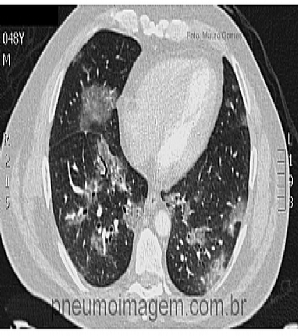

Veja imagens de pneumonia grave no PneumoImagem, clique aqui.